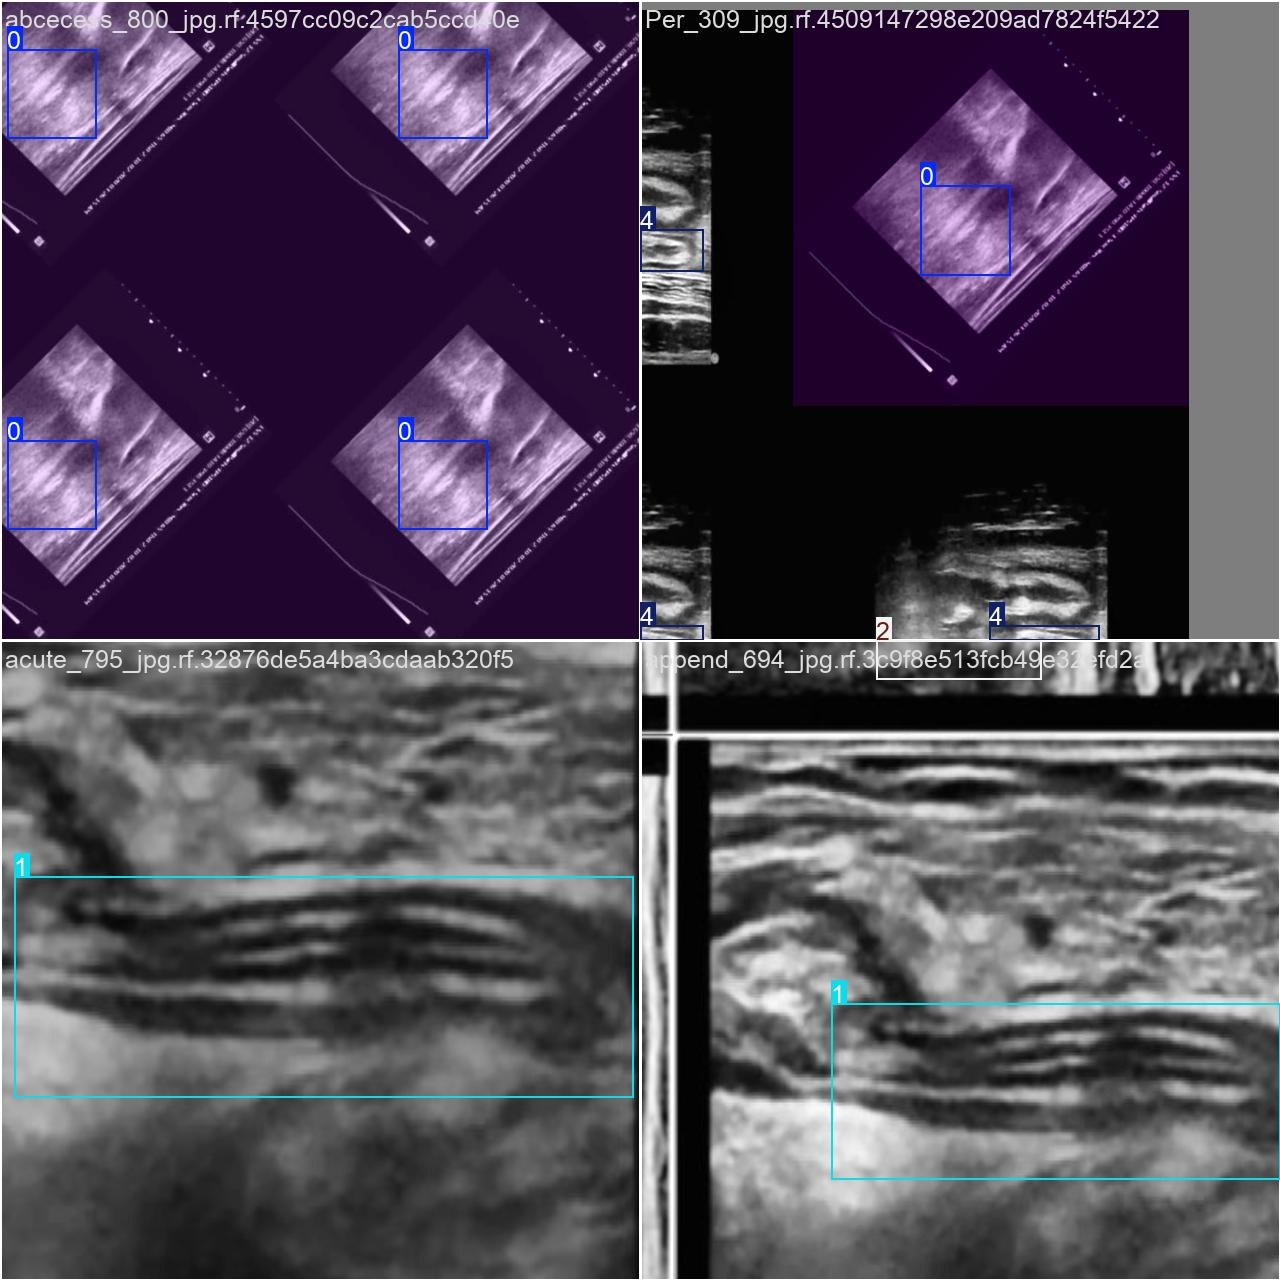

目标检测训练数据可视化

在目标检测训练过程中,该模型在数据处理中的可视化效果重点呈现了各分类目标及其边界框与标签位置的信息。总体而言,在目标识别准确性方面表现出色。尽管当前性能已相对不错,但通过优化数据标注质量和强化模型训练过程仍有机会显著提高检测精度与抗干扰能力。